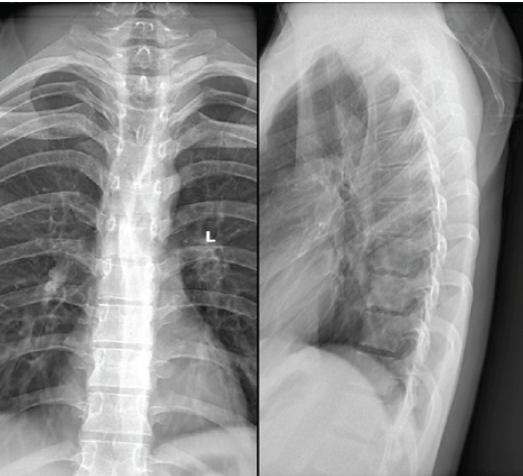

Plain radiographs of the thoracic spine were obtained at presentation. On anteroposterior and lateral views, there was a mild loss of definition of the D1–D2 endplates with minimal reduction of anterior vertebral height at D2. The posterior cortical outline appeared indistinct, although there was no frank collapse or deformity. The overall appearance suggested a destructive vertebral process and prompted urgent cross-sectional imaging (Fig. 1).

Figure 1: Pre-operative radiographs (anteroposterior and lateral views) of the dorsal spine showing irregularity and loss of cortical definition at the D1–D2 vertebral levels with mild anterior height reduction of D2, suggestive of a destructive vertebral lesion.